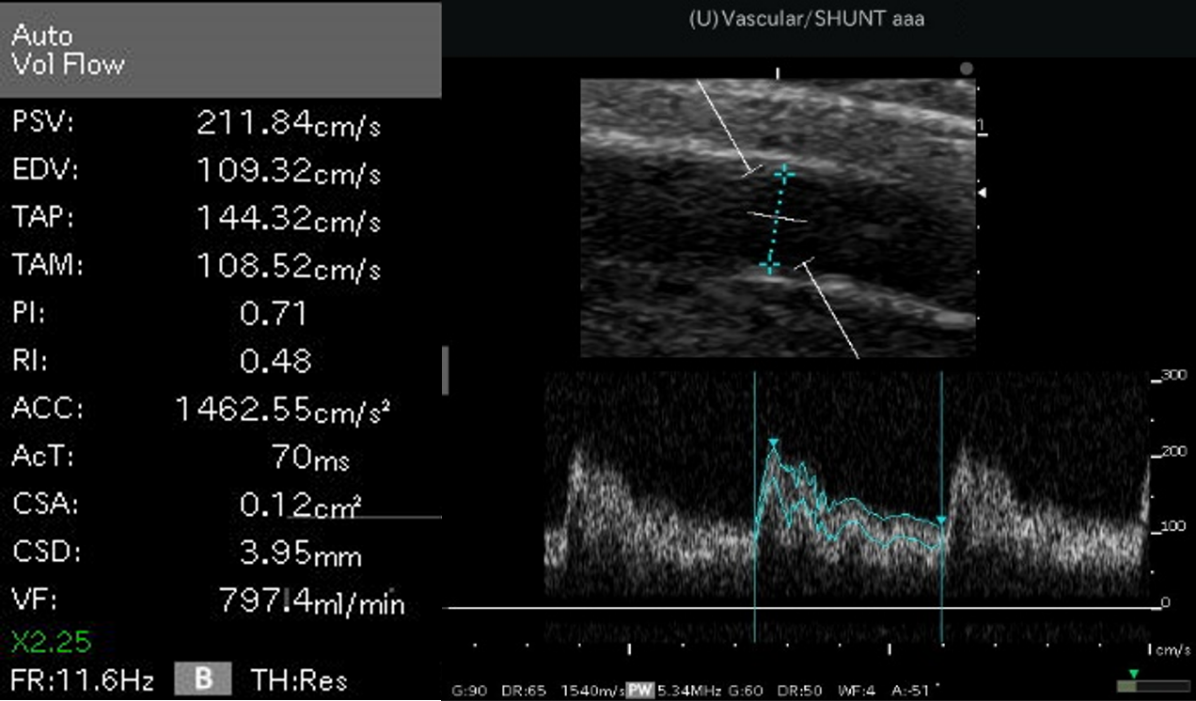

シャント評価

透析患者さんにとってシャント(バスキュラーアクセス)は、まさに生命線と言えます。十分な透析効率を確保するためには、シャントがしっかりと機能していなければならないからです。なので、日ごろからシャントがしっかり機能しているか?不十分ではないか?と評価することが重要です。

エコー装置による直接的評価

近年は小型で多機能なエコー装置が普及し始めましたが、エコーの主要な評価である血流機能評価については技術的な問題から普及しているとは言えません。

当クリニックでは、トレーニングを受けたスタッフがエコーで血流機能評価を行い、合併症の早期発見に向けて定期的な検査を行い、地域の総合病院と連携し早期治療に努めています。

血流機能評価:血流量を数値化して適切な管理を行います。

形態評価:血管の走行・内腔を観察します。